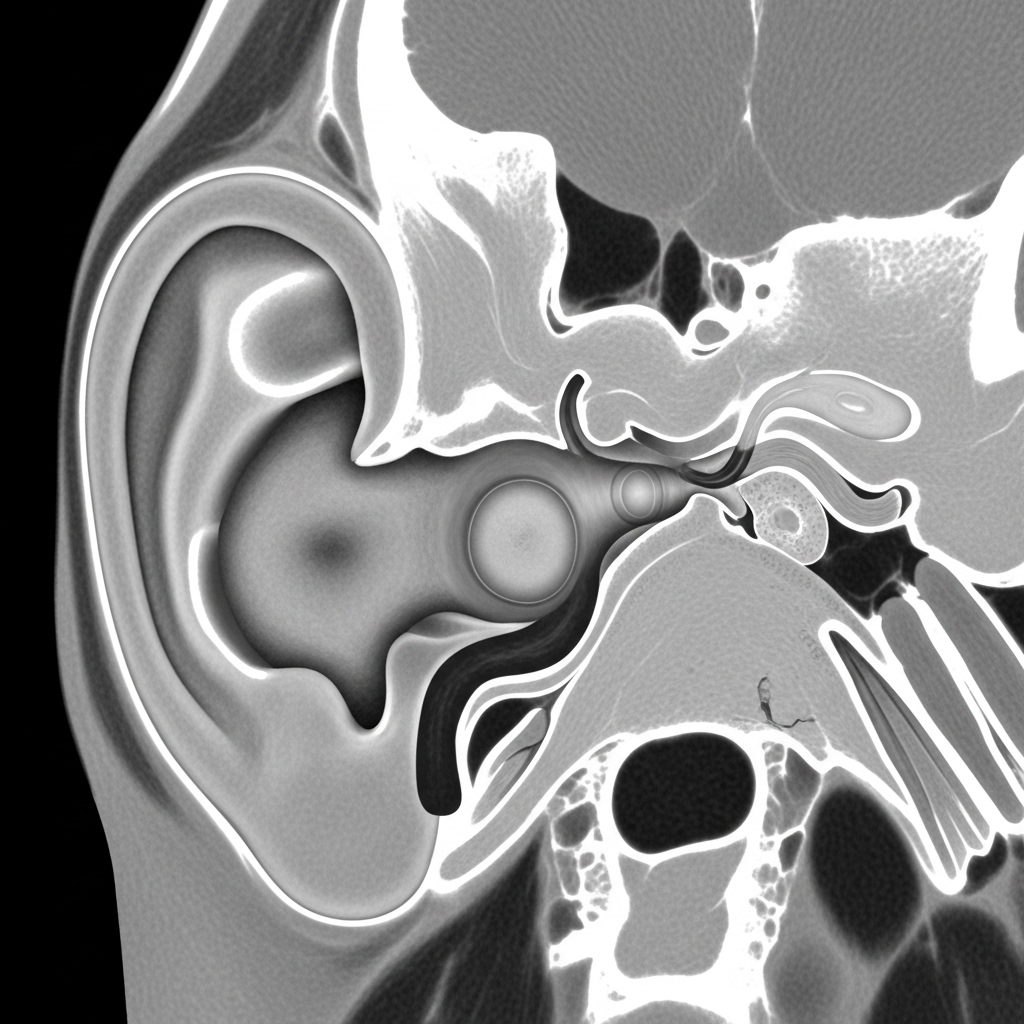

- טומוגרפיה ממוחשבת (CT): סריקת CT של עצמות הרקה (Temporal Bones) היא בדיקת הבחירה להדגמת היקף הכולסטאטומה, מידת הרס העצם, והמעורבות של מבנים חשובים כמו עצב הפנים והאוזן הפנימית. בדיקה זו חיונית לתכנון הניתוח.